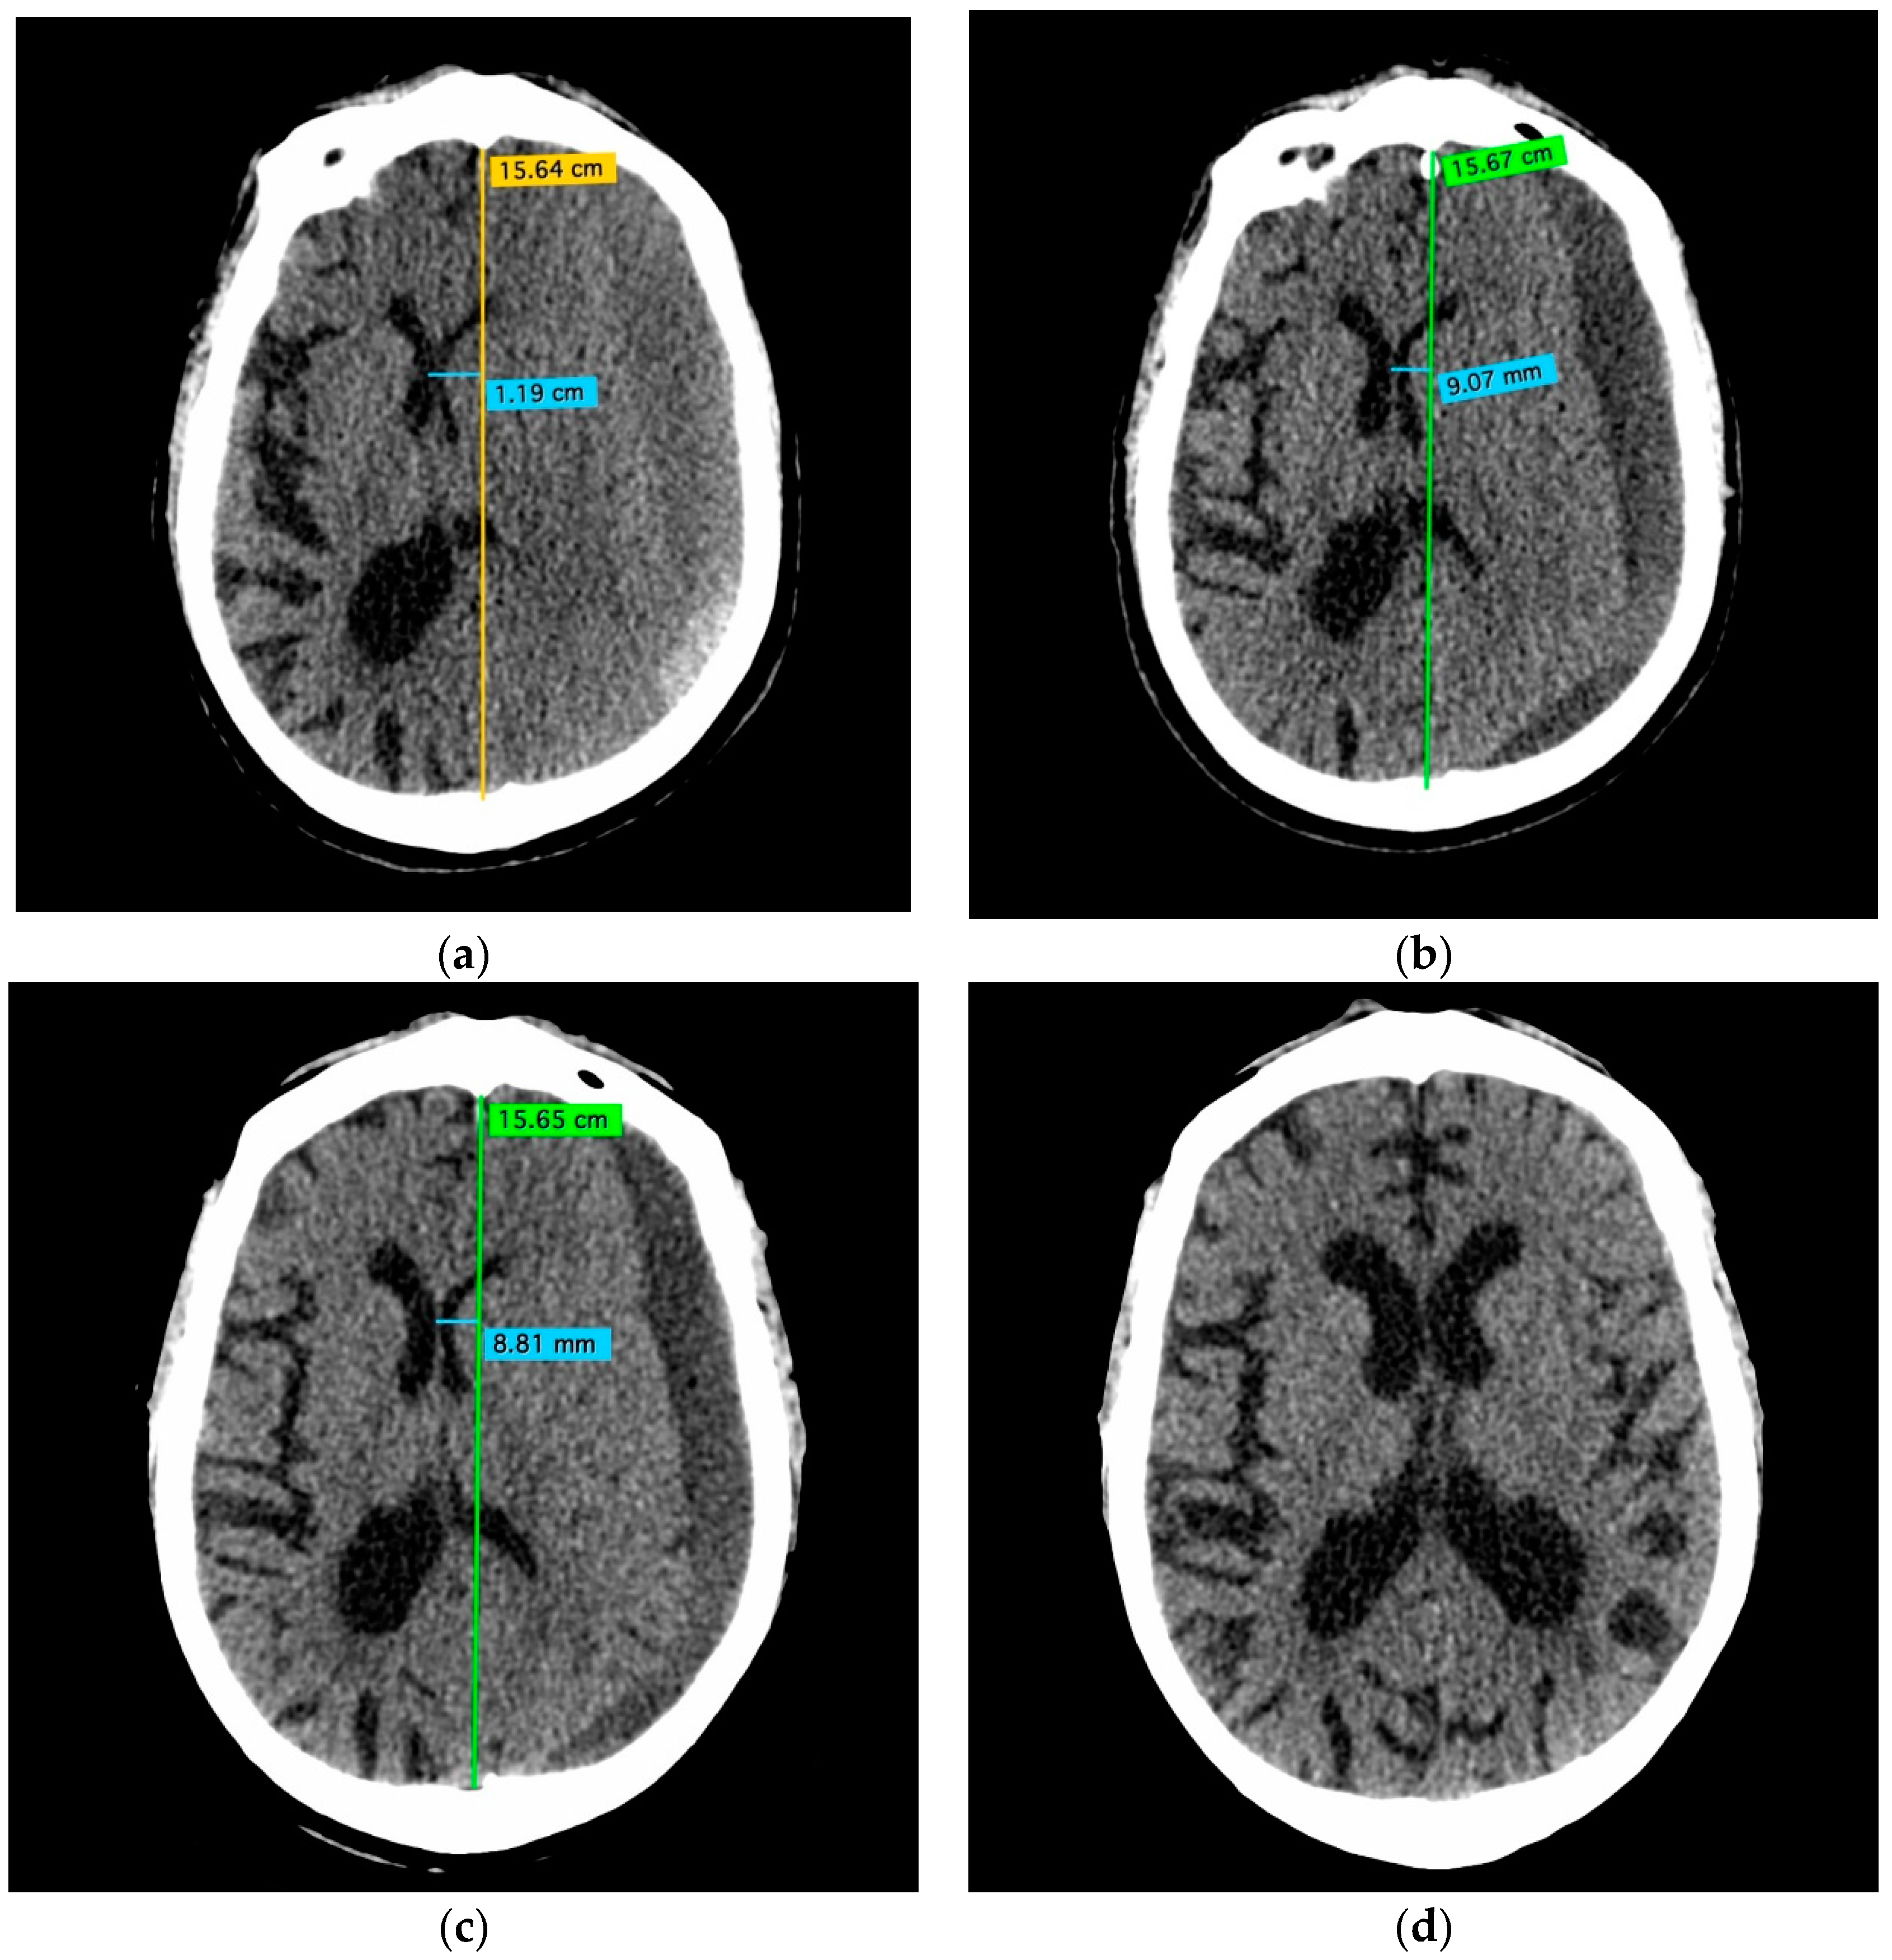

- A 70-year-old patient with left-handed CSDH and a midline shift of 12 mm, motor aphasia, and right-hand hemiparesis.

- A 42-year-old patient with bilateral CSDH that progressively increased during 1.5 months from 54 mL to 69 mL on the right-hand side and from 68 mL to 83 mL on the left-hand side, causing significant compression of both hemispheres and neurological deterioration.

- An 89-year-old patient with bilateral CSDH (no midline shift). There was no apparent connection with an antecedent head injury. However, the patient’s relatives reported that the patient did periodically fall. At the time of admission, the patient presented tetraparesis and a decreased level of consciousness.